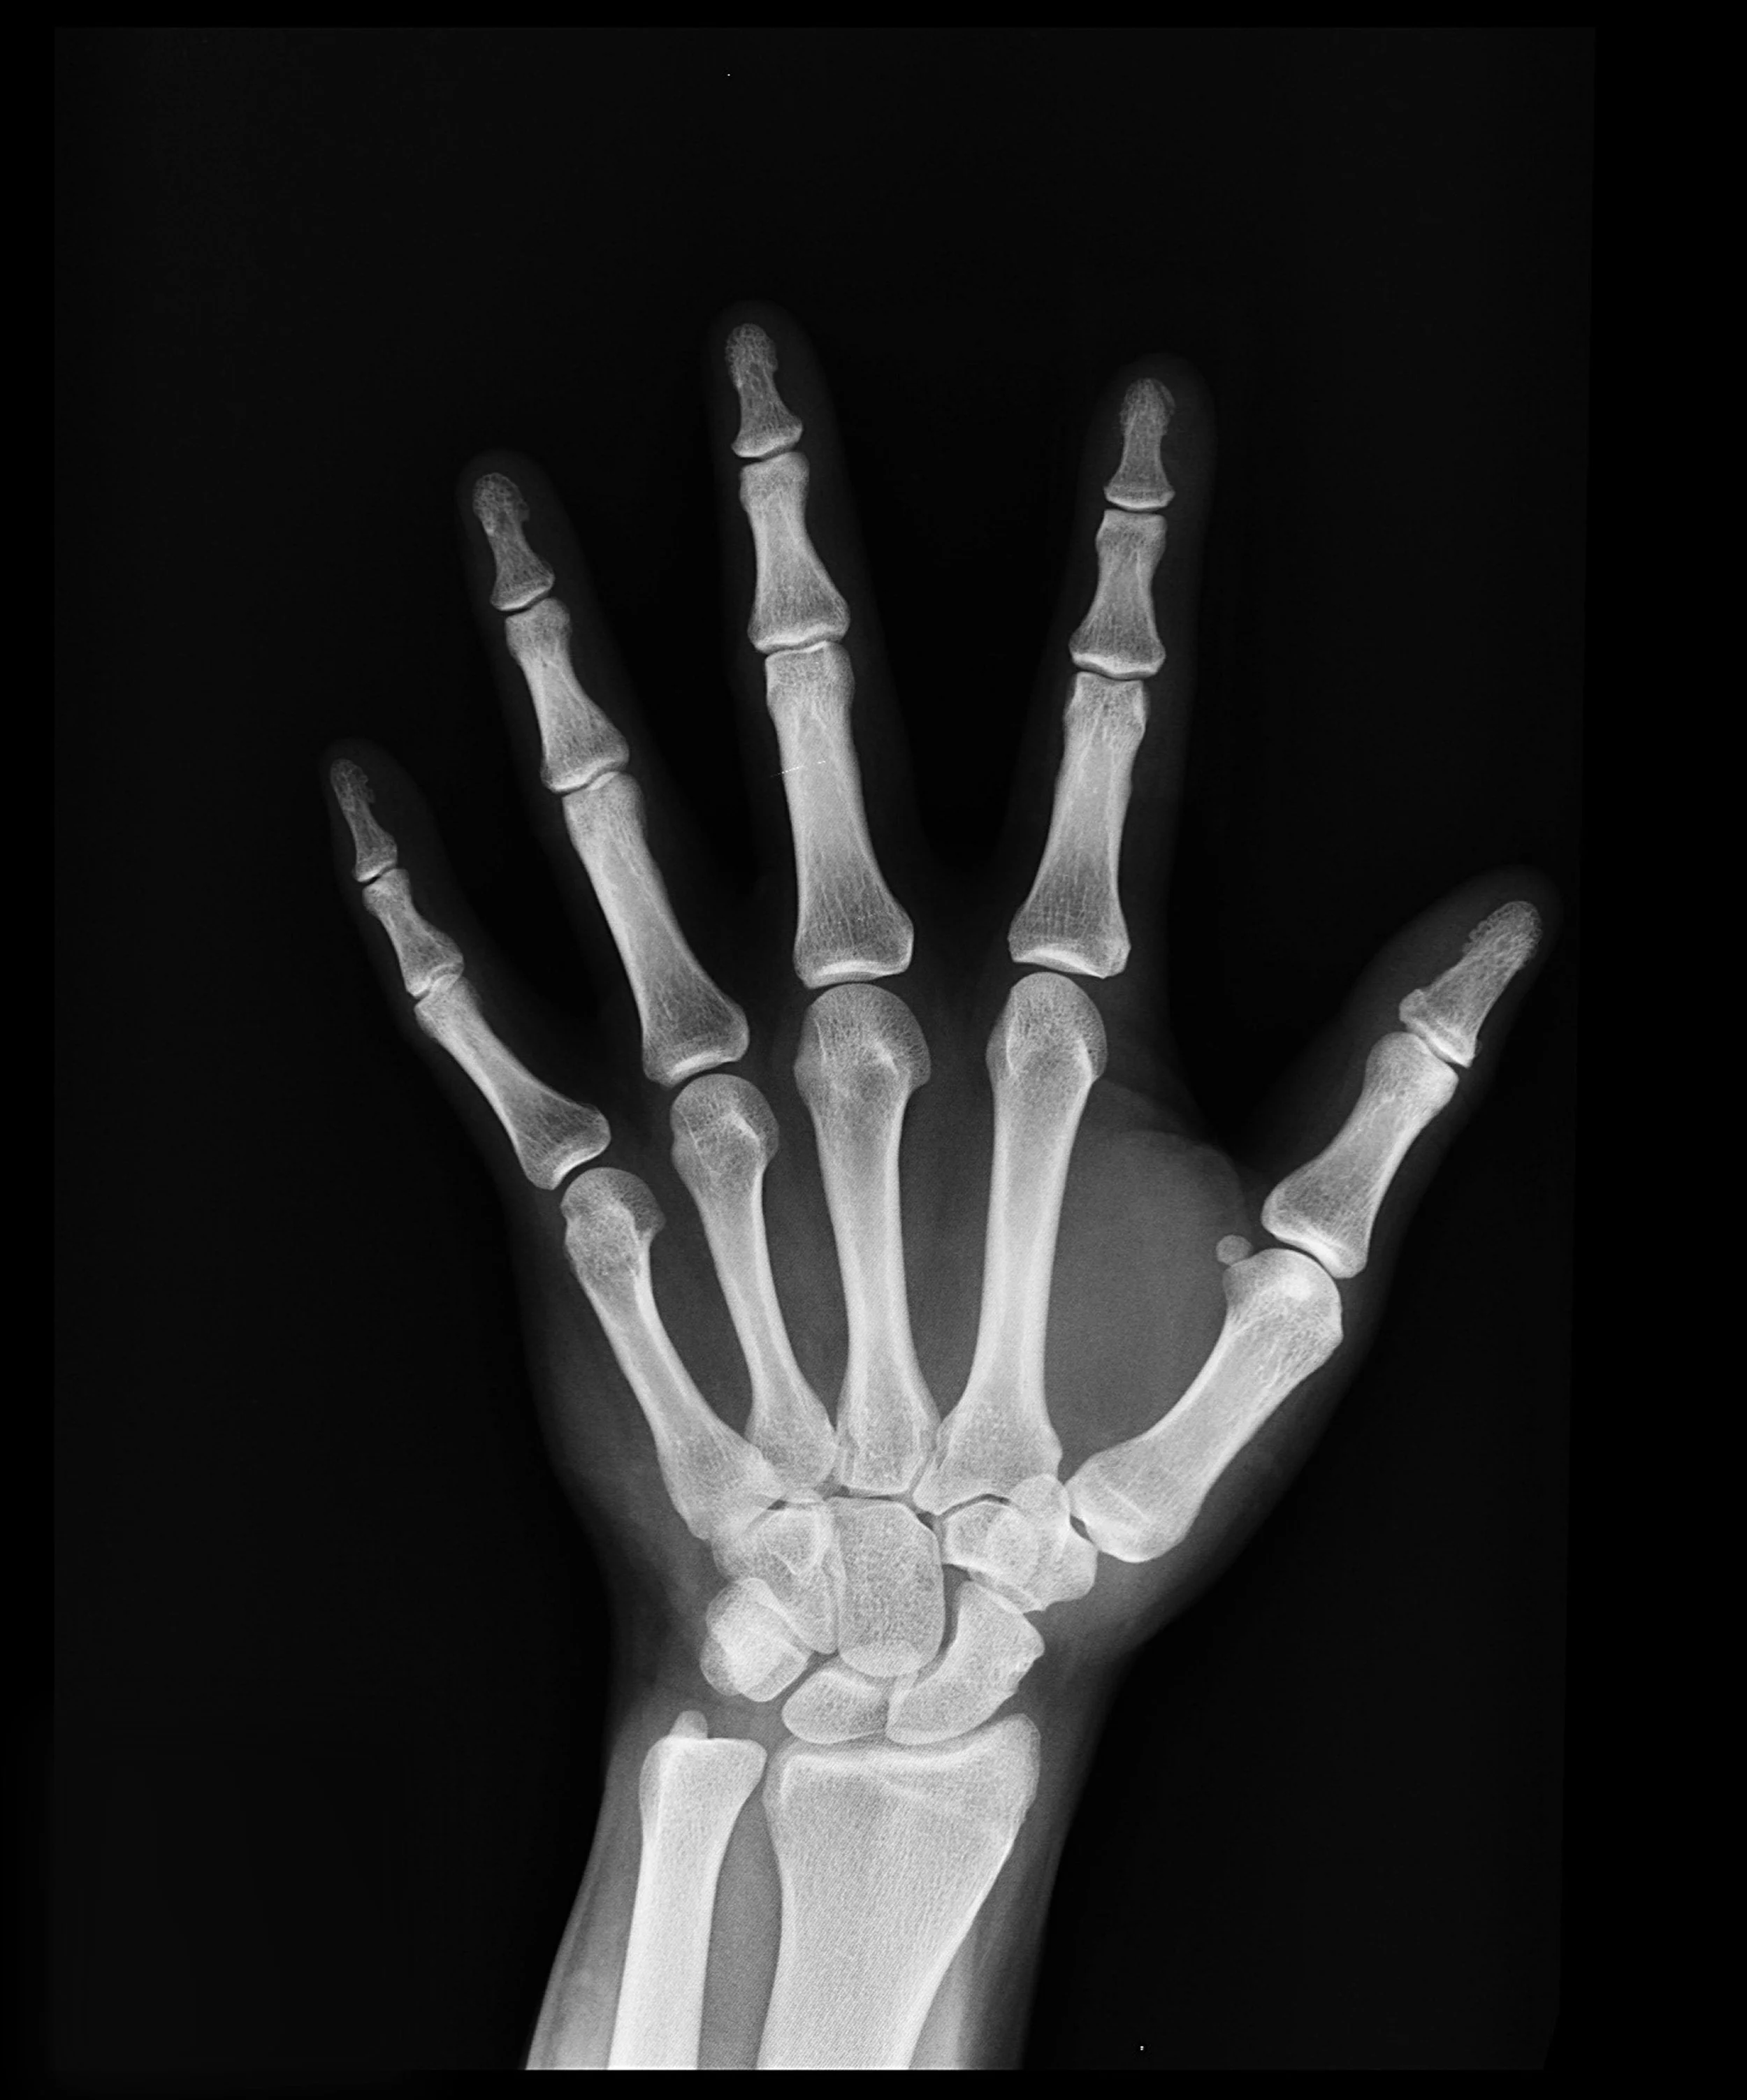

Losing Bone in Your 30s?!

The choices you make today will impact your future.

Frailty is dangerous. It’s scary. It hurts… It happens sooner than we realize.